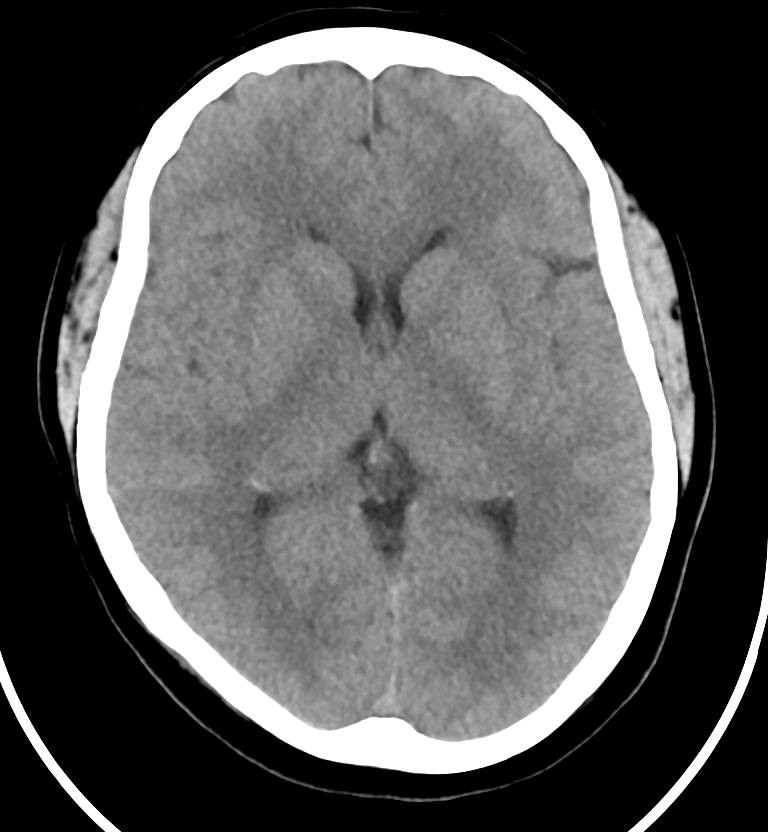

GE 医疗产品线中首个融入英伟达 AI 系统的将会是 Revolution 系列的新型 CT 系统。在加入 AI 系统后,Revolution Frontier CT 的图像处理速度实现了翻倍,将可以提供更快速的肝脏和肾脏检测,减少病人的负担。

图丨 Revolution CT 的成像